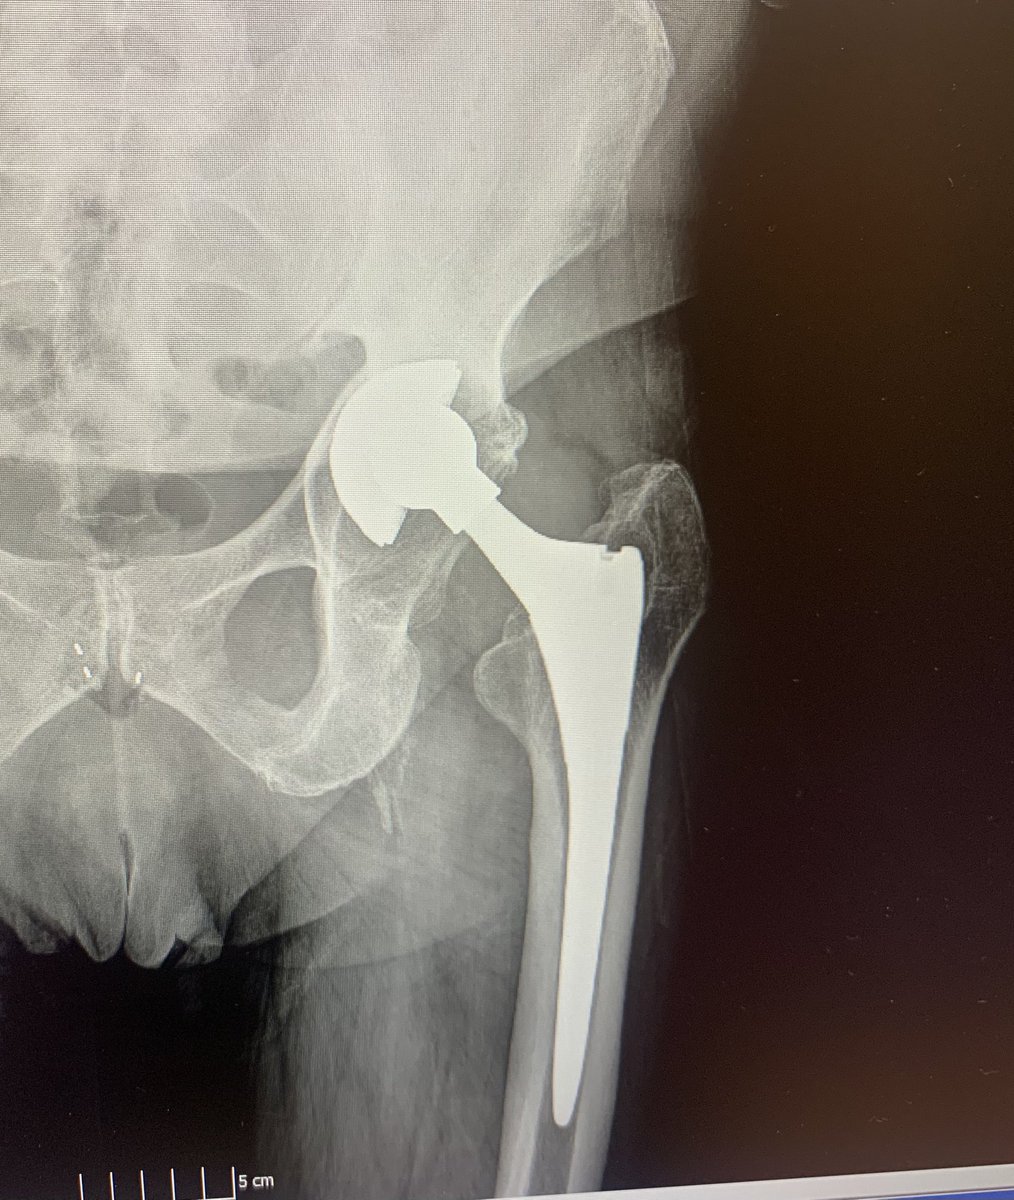

Recently used navigation for the first time in hip revision. #orthotwitter

@generalorthomd @HipReplacement @intellijoint @DeviceNation @NaanDerthaal @jointdocShields